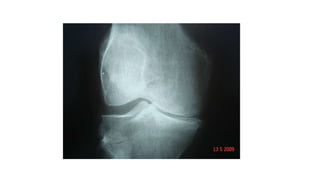

Caso Clínico 2 •Arco de movimento (ADM) encontra-se diminuído moderadamente a direita, com crepitação presente.

A-DIMINUIÇÃO DO ESPAÇOARTICULAR EM PLATÔ MEDIAL B -VISÃO AMPLIADA DO JOELHO DIREITO